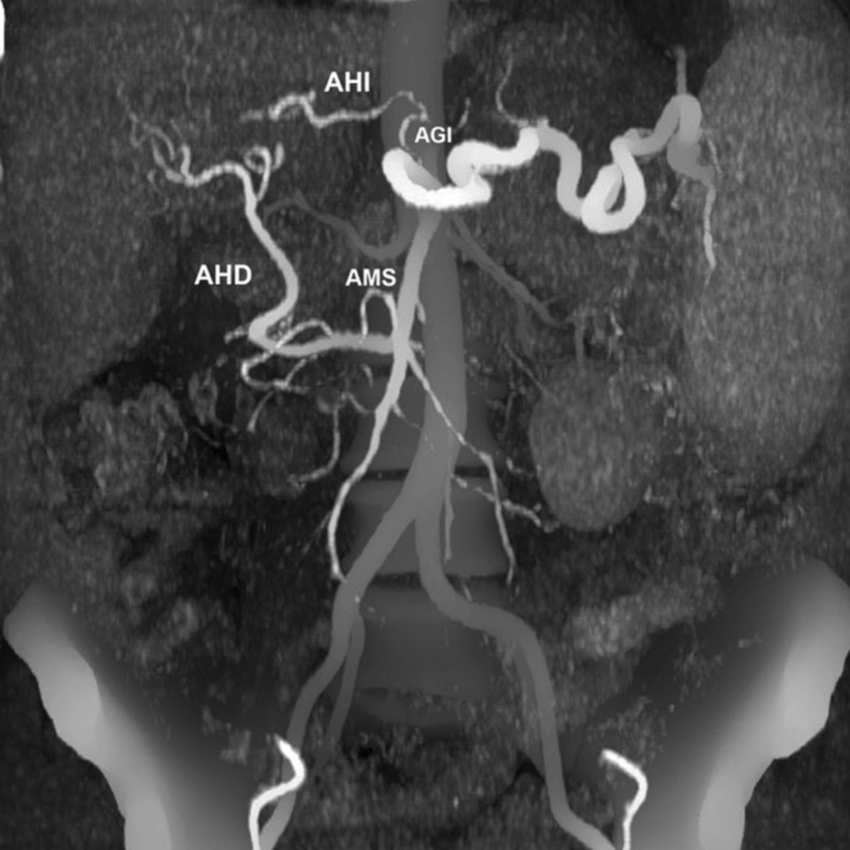

Tipo 9: la AHC emerge de la AMS (Fig. 17).

La población estudiada fue de 275 pacientes, con una edad mediana de 58.5 años y de sexo masculino el 73.1% (n = 201). Se han constatado las variantes tipo 1 (normal) de anatomía de la arteria hepática en 192 casos (69.8%), tipo 2 en 18 casos (6.5%), tipo 3 en 19 casos (6.9%), tipo 4 en 7 casos (2.5%), tipo 5 en 4 casos (1.5%), tipo 6 en 3 casos (1.1%), tipo 7 en 2 casos (0.7%), tipo 8 en 7 casos (2.5%), tipo 9 en 17 casos (6.2%).

La variante anatómica más frecuente de vascularización hepática en esta investigación fue el tipo 1, que hemos encontrado en un 69.8% de nuestra serie. Esta frecuencia es superior a la descrita por Michels5) (55.0%) y Covey et al. (16) (61.3%); no obstante, es inferior a la reportada en la serie de Song et al. (17) (89.1%) y la revisión de Noussios et al. (15) (81.0%) (Tabla 1).

Las siguientes variantes más frecuentes halladas fueron los tipos 2, 3 y 9. Las prevalencias de los tipos 2 y 3 fueron cercanas a la reportada por Fonseca-Neto et al. (18; asimismo, destacamos la prevalencia aumentada de la variante de Michels tipo 9 en nuestra serie comparada con otras publicaciones5,13,15,17,19. Al igual que Covey et al. (16, no hemos detectado la variante de Michels tipo 10; sin embargo, observamos otros hallazgos infrecuentes fuera de la clasificación de Michels, como dos casos de tronco celíaco-mesentérico (0.7%), ausencia del tronco celíaco (emergencia independiente de la AHC y esplénica), AHI accesoria emergente de la AGD y la emergencia de las AHD e AHI aberrantes de la AMS. También hallamos tres casos con arco de Bühler (1.1%), con una frecuencia similar a la de otros reportes (1.0 a 4.0%)20.